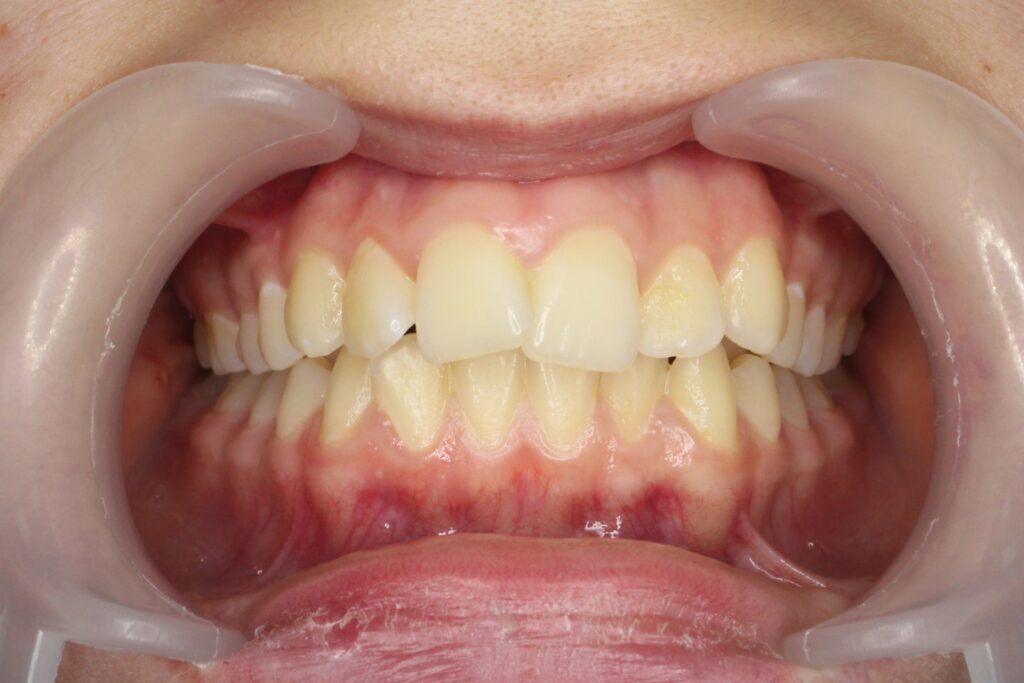

Результат

Была установлена брекет-система Damon Q.

пациент после ортодонтического лечения